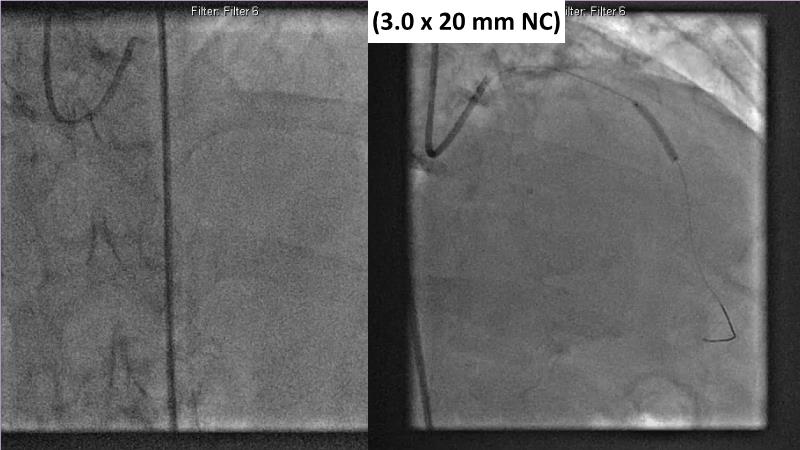

Watch this session to gain case-based insights on using DCBs in complex settings. Learn valuable tips and tricks for optimal DCB application, including the best timing and situations for their use. Discover how to effectively implement a hybrid strategy that combines DES and DCB when needed.

- To get a case based experience on how to use a DCB in complex settings

- To learn about tips and tricks on how and when to use a DCB: the ideal time and situation of DCB application in various complexities

- To utilise the hybrid strategy approach Combining DES and DCB when the situation demands